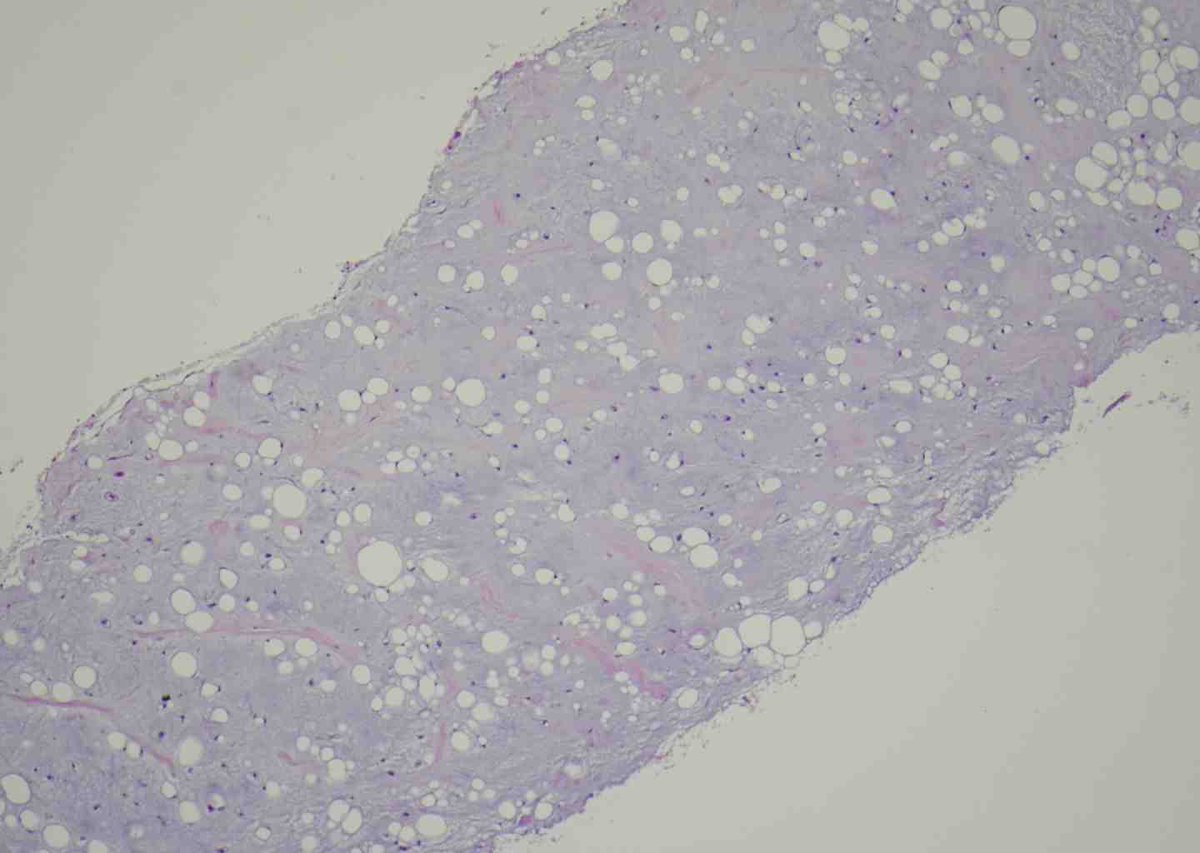

Radiolucency in frontal bone sagittal + axial CT. Here’s a clue: Keep a low power impression Mild expansive remodeling, cortical thinning, radial (spoke) trabecular bone radiating around a central lucency Diagnosis? John Reith Shivani Ahlawat Laura Fayad Lisa Rooper